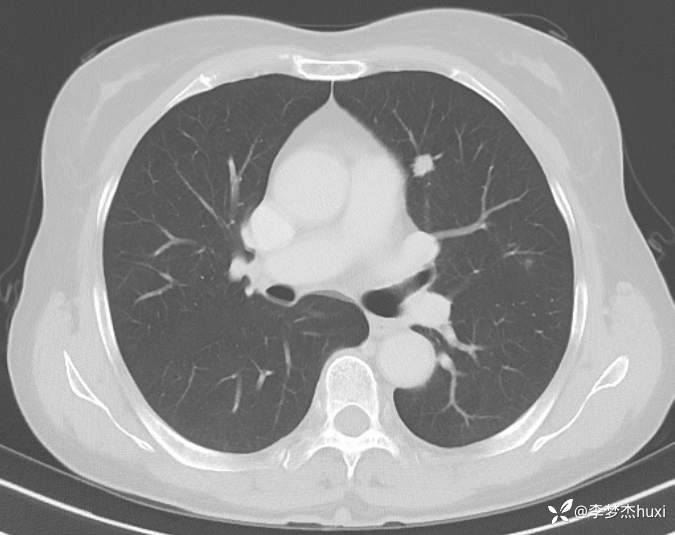

1.现病史:患者老年 女,患者于入院前3天(2024-06-02)体检查胸部CT:左肺部分实性结节,右肺磨玻璃结节,左肺上叶实性结节--性质?建议肺结节门诊会诊检查;双肺索条,双肺下叶条絮状高密度影--考虑肺血坠积效应,主动脉壁钙化,双侧胸膜局部增厚,左侧乳腺钙化点。2024-06-04查胸部增强CT:左肺上叶实性结节--占位?建议结合病理;左肺部分实性结节,右肺磨玻璃结节,建议肺结节门诊会诊检查;双肺索条,主动脉壁钙化,双侧胸膜局部增厚,左侧乳腺钙化点。患者目前无咳嗽、咳痰,无发热,无胸痛,今为求进一步诊治来我院,门诊以“肺诊断性影像异常”收入院。

4.辅助检查:2024-06-02查胸部CT:左肺部分实性结节,右肺磨玻璃结节,左肺上叶实性结节--性质?建议肺结节门诊会诊检查;双肺索条,双肺下叶条絮状高密度影--考虑肺血坠积效应,主动脉壁钙化,双侧胸膜局部增厚,左侧乳腺钙化点。2024-06-04查胸部增强CT:左肺上叶实性结节--占位?建议结合病理;左肺部分实性结节,右肺磨玻璃结节,建议肺结节门诊会诊检查;双肺索条,主动脉壁钙化,双侧胸膜局部增厚,左侧乳腺钙化点。。